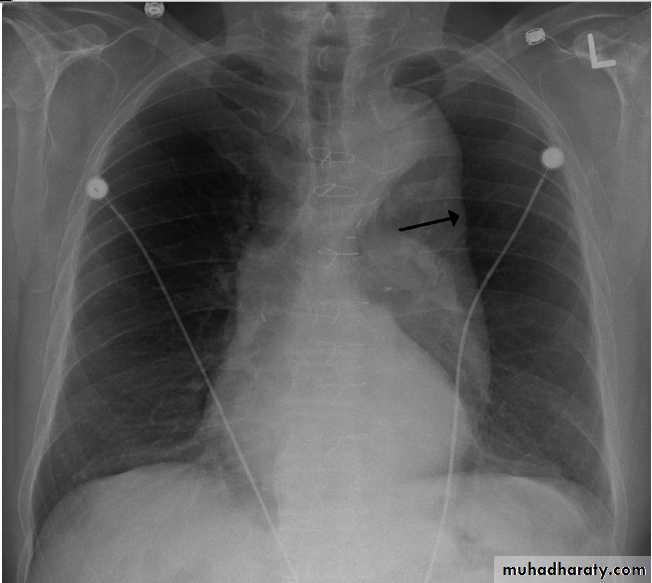

On a posteroanterior chest x-ray (A), the left hemithorax is very dark or lucent because the left lung has collapsed completely (white arrows).The tension pneumothorax can be identified because the mediastinal contents, including the heart, are shifted toward the right, and the left hemidiaphragm is flattened and depressed. A computed tomography scan done on a different patient with a tension pneumothorax (B) shows a completely collapsed right lung (arrows) and shift of the mediastinal contents to the left.

Tension Pneumothorax. Portable chest film in a 43-year-old woman with ARDS shows a large right pneumothorax with mediastinal shift and ipsilateral diaphragmatic depression, suggesting tension.

Air was evacuated under pressure during emergent placement of a right chest tube.